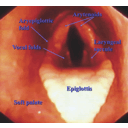

Endoscopic View of the Larynx.jpg